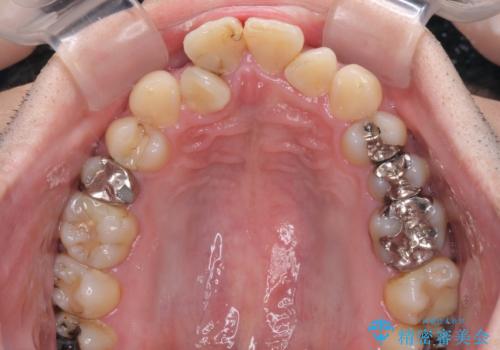

重なって磨きにくい上下の前歯 ワイヤー装置での抜歯矯正

- 前歯のデコボコを改善したいと来院された患者様です。

口元の突出感はないものの、上顎前歯のデコボコが著しかったため、上下顎左右小臼歯4本を抜歯することとしました。

上下の正中位置を改善するため、右下は第一小臼歯を、その他は第二小臼歯を抜歯することとしました。